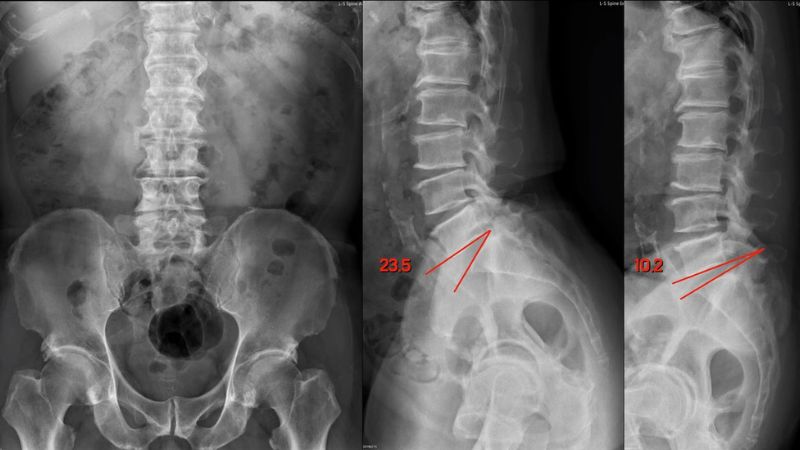

- Chụp X-quang cột sống giúp nhận diện vị trí và mức độ hở eo, đánh giá tình trạng biến dạng hoặc trượt đốt sống.

- Chụp CT cắt lớp vi tính cung cấp hình ảnh chi tiết về cấu trúc xương, giúp bác sĩ phát hiện rõ vết nứt, khuyết hoặc tổn thương ở mấu khớp, ống sống.

- Chụp cộng hưởng từ (MRI) để kiểm tra tổn thương mô mềm, đĩa đệm, rễ thần kinh và tủy sống. Theo đó, bác sĩ sẽ kiểm tra được mức độ chèn ép và lựa chọn phương pháp điều trị phù hợp.

Nhờ những kỹ thuật này, bác sĩ có thể xác định giai đoạn bệnh, phân biệt với các nguyên nhân đau lưng khác như thoát vị đĩa đệm hay hẹp ống sống. Qua đó, bác sĩ sẽ lên được phác đồ điều trị bệnh lý an toàn và hiệu quả nhất.